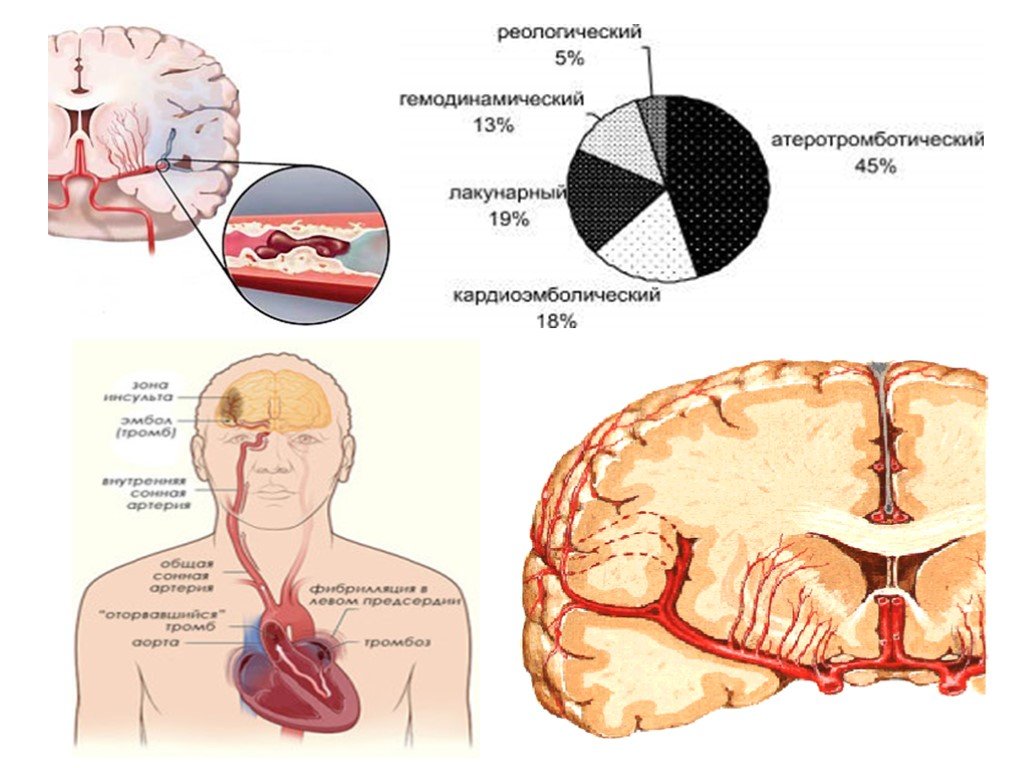

Анатомия: Задняя соединительная артерия мозга